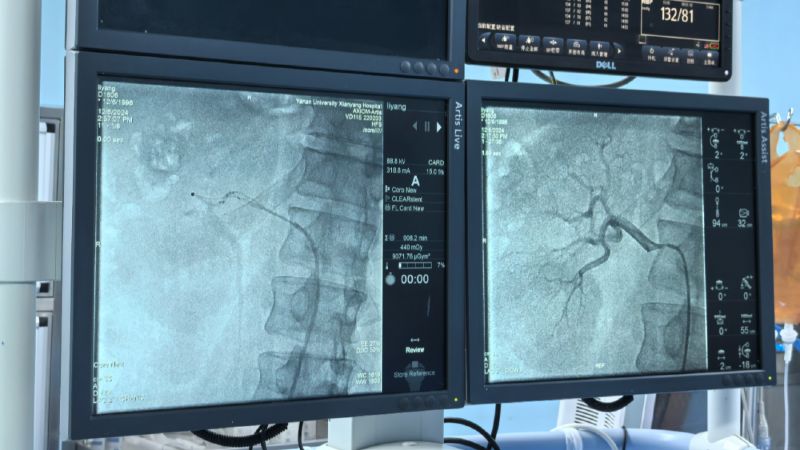

术中通过对左右肾动脉造影,了解肾动脉解剖结构、评估肾脏灌注情况。而后顺利将射频消融导管的电极头推至肾动脉主干及分支中远段,双侧肾动脉累计消融16次,涵盖相应分支及主干,共完成78个有效消融点,完成后再次行双肾动脉造影,评价手术对肾动脉形态和肾血流影响,累计用时仅60分钟高效圆满完成。术前血压由154/110mmHg,手术完成后血压130/94mmHg,即刻血压下降效应明显,直至目前术后减少三种降压药物,监测血压维持在120/70mmHg左右,手术效果理想,长期血压下降情况我们将持续随访关注。